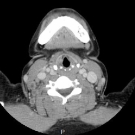

A 37-year-old woman with no related medical history presented to the clinic with right-sided neck swelling. She reported having had swelling in the area for approximately 6 years, but she had recently noted...

07/29/2021